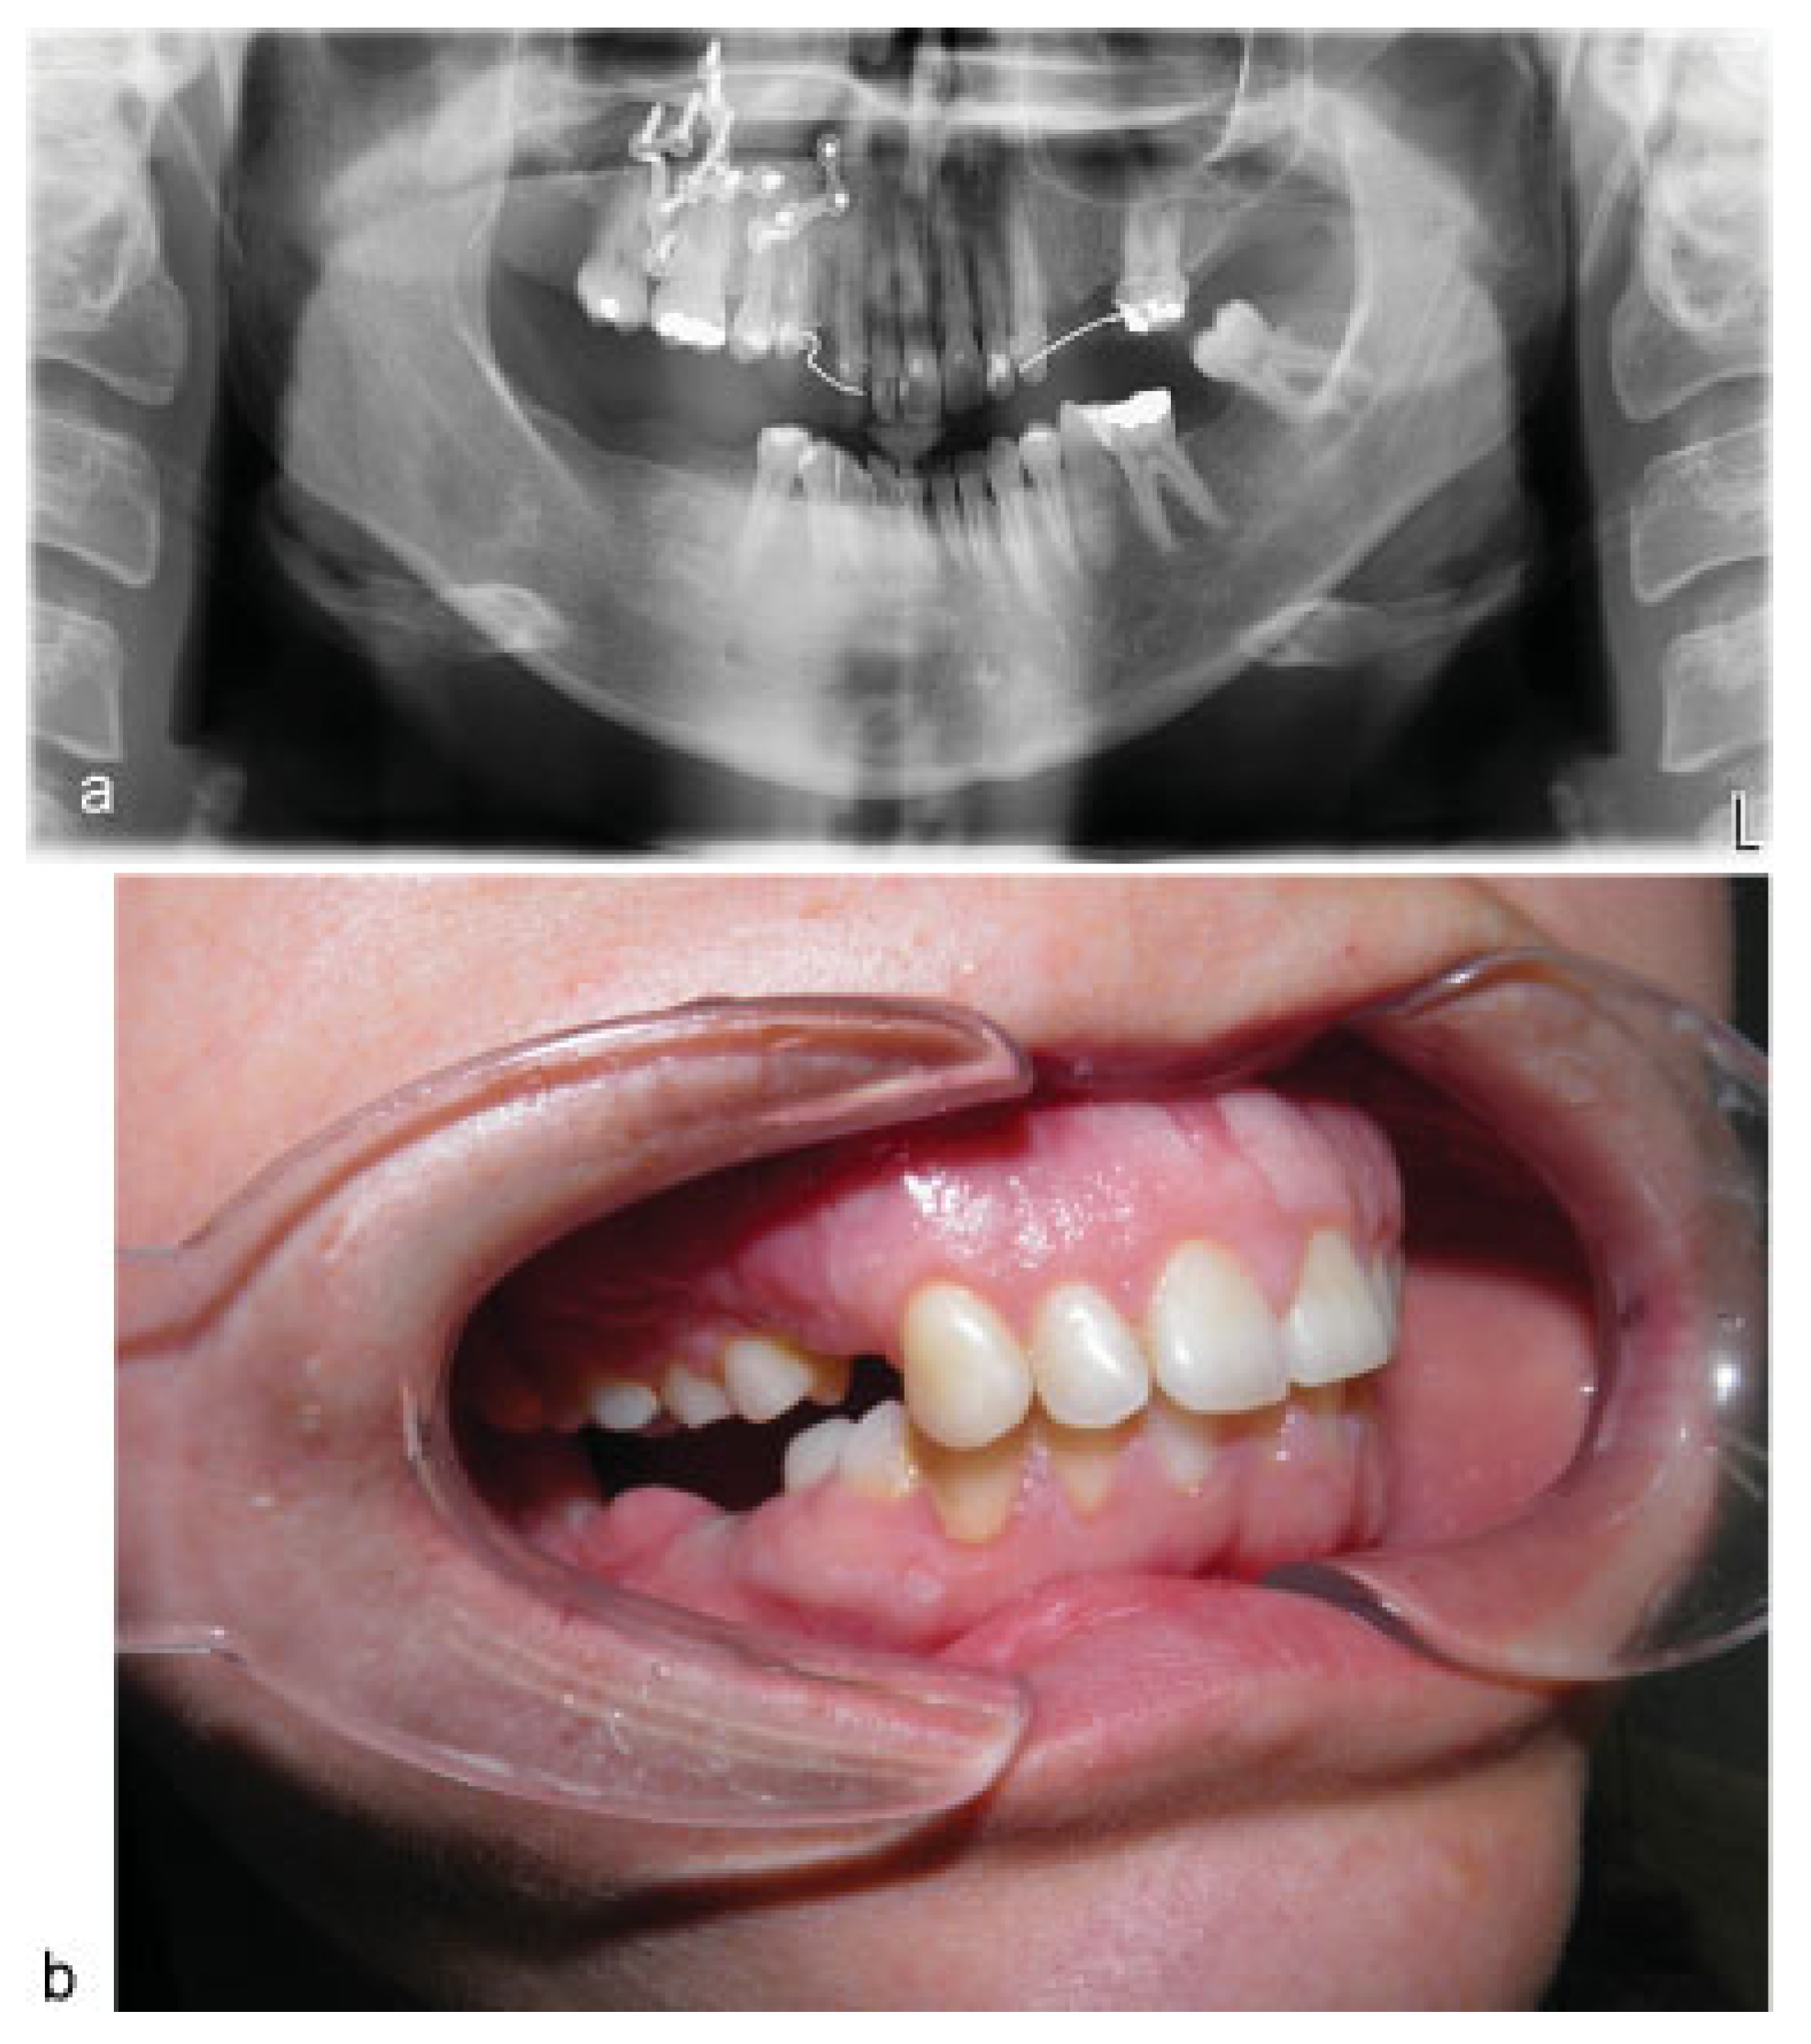

Figure 4. (a,b) OPT X-ray and intraoral view after surgery.